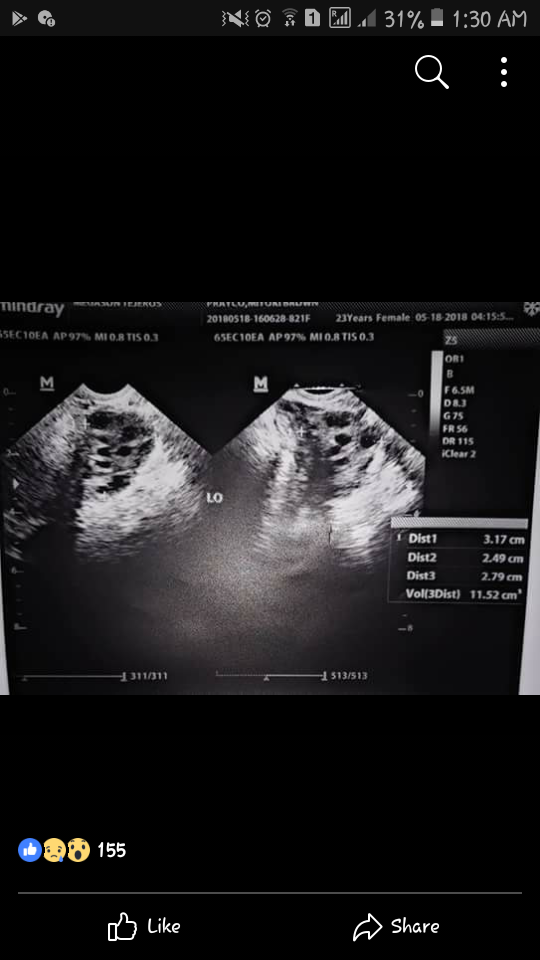

Way back month of May I was expected a baby 🖤 kase ang alam ko magaling na ko. 2mos akong delay, and same sya ng symptoms, gaining weight, cravings, bigat ng pakiramdam, pananakit ng boobs, ang dalas pa ng times na nagno nose bleed ako na di ko alam kung bakit. Same story nag PT ako but this time may nagpo positive, and negative. So para sa ikakalma ng utak ko, nagpa transvaginal ulit ako to find out na dalawang ovary ko na ang may PCOS. Yes bumabalik sya and malala pa is yung kumakalat at nanganganak sya. 💔